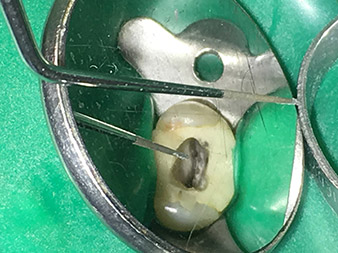

Efficient and atraumatic root canal treatment

Alongside efficient diagnostics and treatment methods, the use of the latest technical aids and instruments also makes an important contribution to successful patient care. Dr Shahrad Nouraie Ashtiani and his team at the practice in Bremen, Germany, treat up to ten endodontics cases a week. Patients’ desires for treatment which is as atraumatic as possible combined with good prognoses for success present a daily challenge for the dentist and oral surgery resident specializing in endodontics.

As an avid user of the expanded W&H instrument range for ultrasonic endodontics, Dr Nouraie Ashtiani is not only able to perform root canal treatments more efficiently but also to do so in a way which puts less strain on the patient. The dental expert masters even the most difficult of situations with ease. In a recent interview, the specialist in endodontics told us about the particular features which characterize the W&H instruments and mentioned possible risks which can arise in root canal treatment.

Dr. Nouraie: Yes, in my opinion. The tips allow you to work in a particularly atraumatic and minimally invasive manner. Among other steps, this applies to the exposure of the individual canal accesses, preparation of the cavity in the area of the pulp chamber, rounding off of the canal openings at the transition from the bottom of the chamber to the root canal and preparation of the coronal regions of the root canals.

Dr. Nouraie: The use of ultrasonic tips allows targeted, atraumatic, minimal removal of substance at the desired site (e.g., when exposing the canal openings, rounding off the cavity floor and exposing broken-off instruments or posts as well as when processing coronal canal sections).

Canal transitions can be smoothed and rounded off with more precision than when using burs. The activation of the rinsing fluid in particular offers enormous advantages that cannot be guaranteed with other instruments. The special instruments from W&H make it possible to perform completely new indications minimally invasively such as revision of broken-off tips and posts.

Visual aids such as dental loupes or even better a surgical microscope should be employed for all indications in the canal. In addition, I also think it is important that all the applications in the canal – with the exception of the activation of the rinsing fluid – are performed by specialized colleagues with corresponding experience and the necessary expertise in the field.